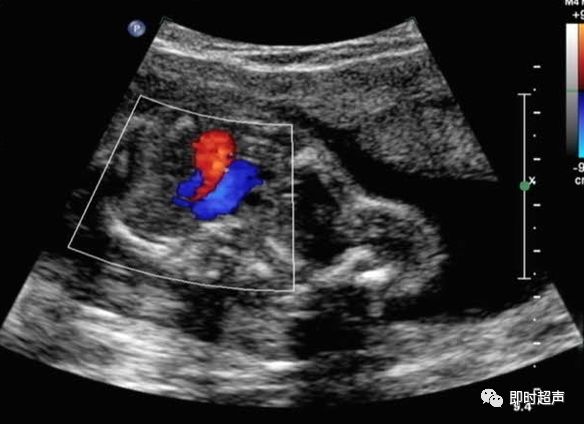

主动脉弓离断

主动脉弓离断定义:升主动脉与降主动脉之间的主动脉弓离断,下肢血供通过动脉导管由右心提供。分类主要根据中断位置与头臂血管的相对关系。A型:左锁骨下动脉远端中断。B型:左颈总动脉远端中断。C型:头臂干远端中断。

解决方案:

显示三血管气管切面时侧动探头,显示主动脉弓肺动脉汇入降主动脉